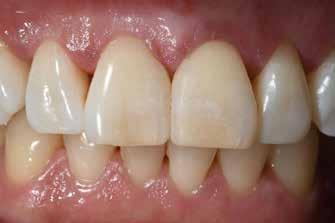

ezen a területen, a fogászat profitál az ilyen fejlesztésekből, és ma már számos kezelési megoldást kínálunk pácienseinknek. Rezidens korom alatt klinikai szakfelügyelőként dolgoztam akadémiai környezetben, ahol elsősorban kivehető fogpótlásra szoruló geriátriai betegeket kezeltem, valamint olyanokat, akiknek fix fogpótlásra, például fog- vagy implantátummal ellátott hagyományos rögzített fogpótlásra (azaz korona és híd) volt szükségük, elsősorban arany vagy fémkerámia felhasználásával. Az ezekben az években megfigyelt klinikai kudarcok és a beavatkozások invazív jellege, nevezetesen a foghúzásra vonatkozó több fúrás és egyszerűbb döntések jelentős szerepet játszottak a kutatási irányvonalam kialakításában az évek során. Ez volt az az időszak is, amikor elkezdtem többet foglalkozni az adhezív fogászattal, ami megváltoztatta a protetikai fogászat klasszikus arculatát, és határozottan kevésbé invazívvá tette azt (1. a-d ábrák). Ma, az intenzív transzlációs és klinikai kutatás eredményeként, különös tekintettel a fogászati bioanyagok alkalmazására, klinikai szakértelmem a minimálisan invazív, adhezív eljárások alkalmazására összpontosít a protetikai fogászatban, a szövődmények kezelésére és a költséghatékony kezelési lehetőségek felkínálására.

1. a-d ábrák: a) Fogerózió a molárisok okkluzális felszínén, b) maratás foszforsavval, c) minimálisan invazív műgyanta-kompozit fedőréteg levegővel történő felszívása, d) adhezív ragasztott fedőréteg a hiányzó zománc és dentin helyreállítására.

kező fogerózió problémájával is, amely a mineralizált fogszerkezet elvesztésének egyik fő oka, az eróziós étrend extrinsic savai vagy intrinsic etiológia, például anorexia, bulimia nervosa vagy gyomorreflux következtében.